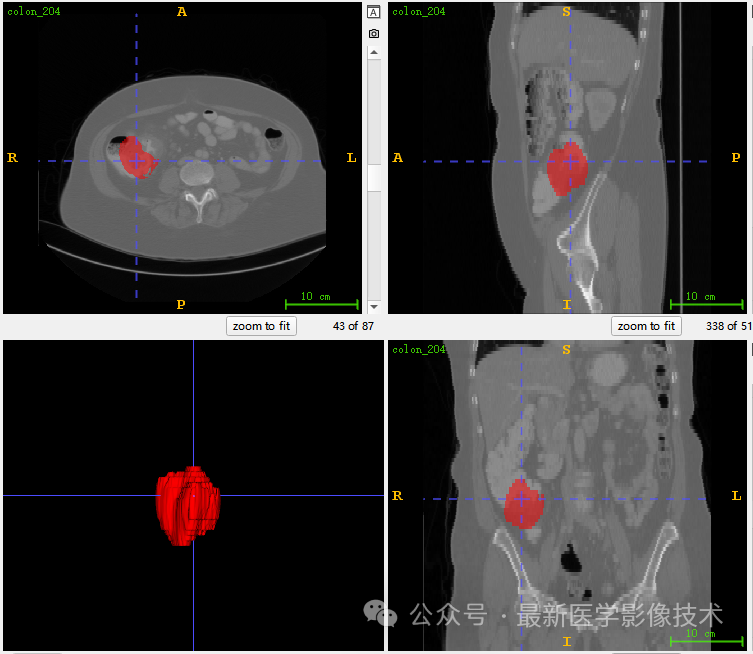

5、验证集分割结果

左图是金标准结果,右图是预测结果。